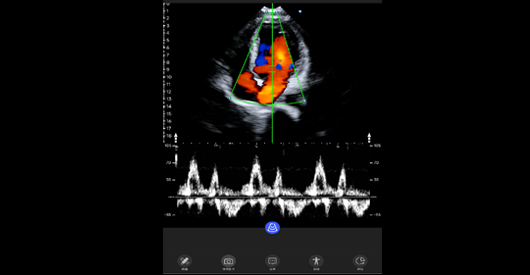

心脏左心室血流频谱

中心频率:3.6 MHz。带宽范围:2-5MHz。